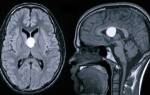

Головные боли можно разделить на четыре основных типа. Боли первого типа связаны с органическими повреждениями головного мозга. К этому типу относятся боли, вызванные такими воспалительными заболеваниями мозга, как менингоэнцефалит, менингит и т.д. Боли при черепно-мозговых травмах тоже можно отнести к первому типу.

Также сюда относится головная боль, связанная с новообразованиями головного мозга. Характер болей данного типа может быть различным, но для большинства вышеперечисленных заболеваний свойственен ряд симптомов, то есть клиническим проявление болезни является не одна головная боль, а головная боль в сочетании с другими симптомами (тошнотой, рвотой, расстройствами сознания, неадекватным поведением и т.д.).

Что же делать, когда жажда и частое мочеиспускание не дают спокойствия даже ночью, а глюкоза в норме? Ответ прост. Это проявления несахарного диабета, при котором уменьшается количество вазопрессина. Заболевание связано с поражением центральной нервной системы, ведь гормон вырабатывается в гипоталамусе. Опухоли, травмы, воспалительные реакции являются причинами болезни. Единственный способ лечения – пожизненный прием гормонов.

Если врач заподозрил какое-то заболевание, он может назначить дополнительное обследование. Например, экскреторную урографию при заболеваниях почек, исследование глазного дна при сахарном диабете, МРТ головы при недостатке вазопрессина.